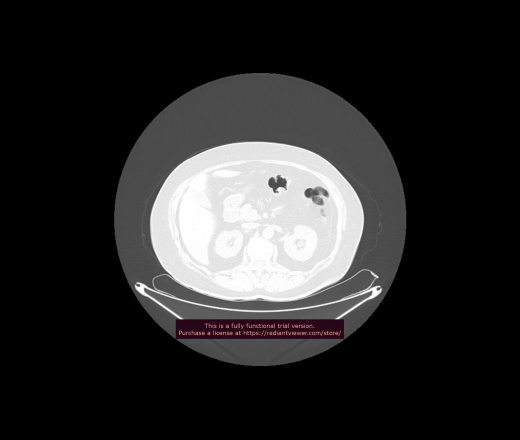

Уважаемые коллеги, если имеется интерес, сможете ли Вы спрогнозировать дальнейшее +-одинаковое течение процесса у 4 данных разных пациентов? Зацепиться где-то можно очень просто, где-то нельзя.